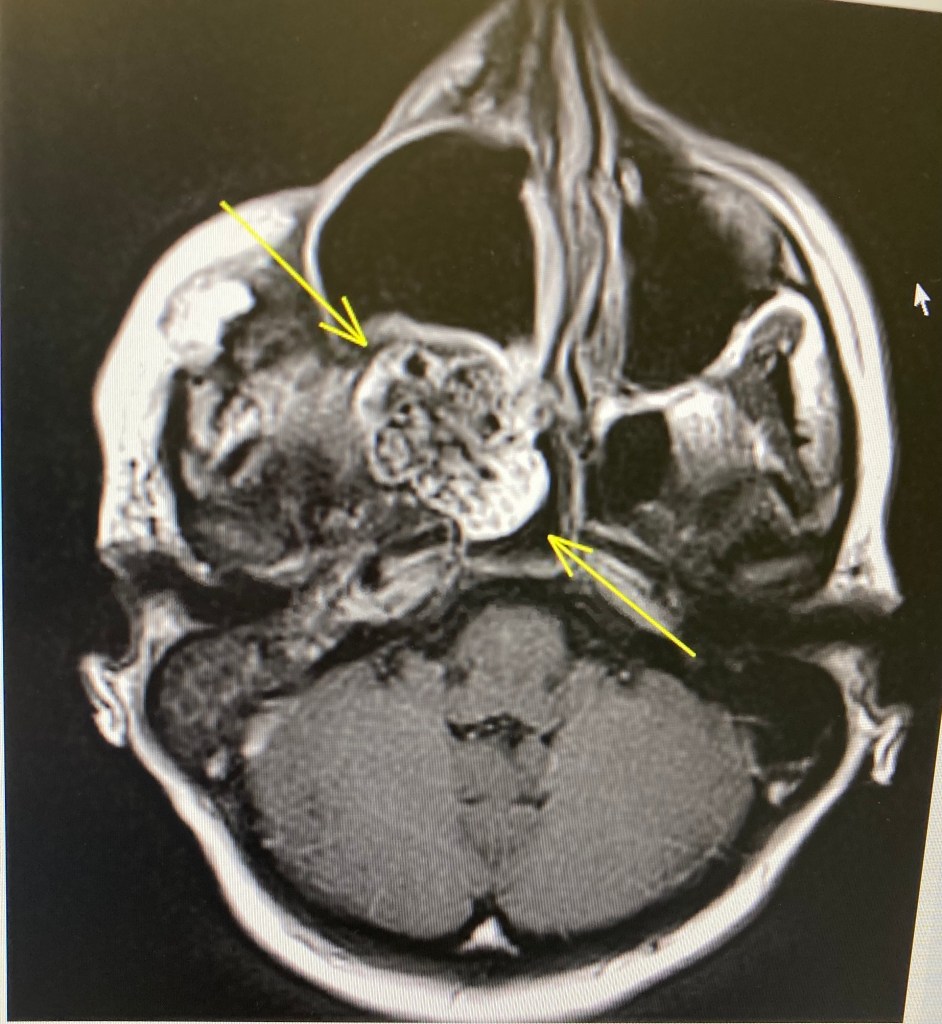

They doubt they’ll be able to cut it out. It’s too big, the location is tricky. Certainly at this stage, it would be dangerous to try. If they cut into it but couldn’t get it all and left some there, the disturbance would make it run away on us scarily quickly. And considering how scary its speed is already, I don’t want to find out what that means. I have to come to terms with this reality, but I will hold out some hope that somehow, they will eventually find a way to remove it in a safe-ish way, after the chemo. We will discuss the possibility of surgery after the chemo. There are also some other back pocket options to maybe look at later to slow its growth (like the new and exciting TKIs just coming on the market)

Chemo does not shrink osteosarcoma. Though weirdly, mine has come back in the soft tissue, not actually in the bone. They don’t really know how it’s going to react. Maybe, just maybe there is a glimpse of hope that it could shrink a bit (though unlikely).